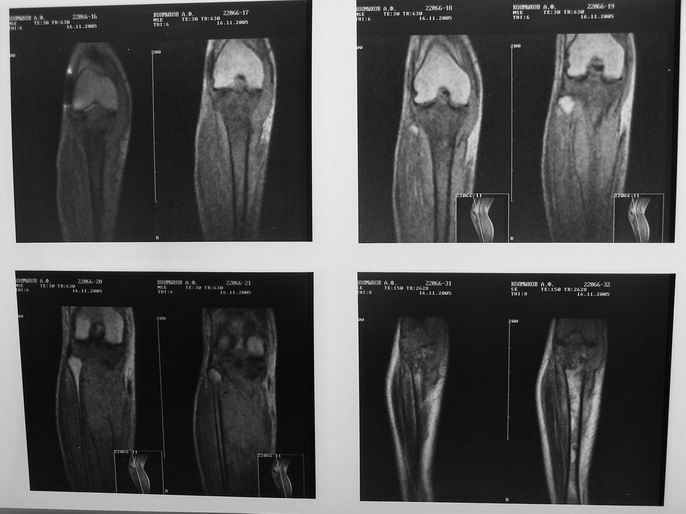

Всем привет!Кому интересно - может лицезреть мое личное наблюдение первичной костной лимфомы с поражением правой большеберцовой кости (см. аттач). Пациент: мужчина, 46 лет. Анамнез прослеживается в течение 1,5 лет - начало заболевания с появления болей.С уважением, Виталий Тазалов.

Ещё одно клиническое наблюдение - лимфома кости, до и после ПХТ и лучевой терапии.